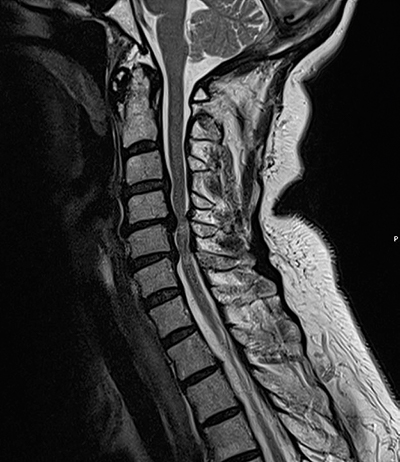

Axial T2-viktad MR-bild mellan C4 och C5 på en 68-årig kvinna med balanssvårigheter, klumpighet och radikulopati mot händerna. I status fanns bilateralt positivt Hoffmanns tecken och stegrade reflexer. I bilden ses en bredbasig diskbuktning och fasettledshypertrofi som försnävar spinalkanalen.

T2-viktad MR-bild med diskbuktningar och ligamentum flavum-hypertrofi som orsakar ryggmärgskompression C4/C5 samt C5/C6. Därutöver ses signalförändring i ryggmärgen på motsvarande nivåer.